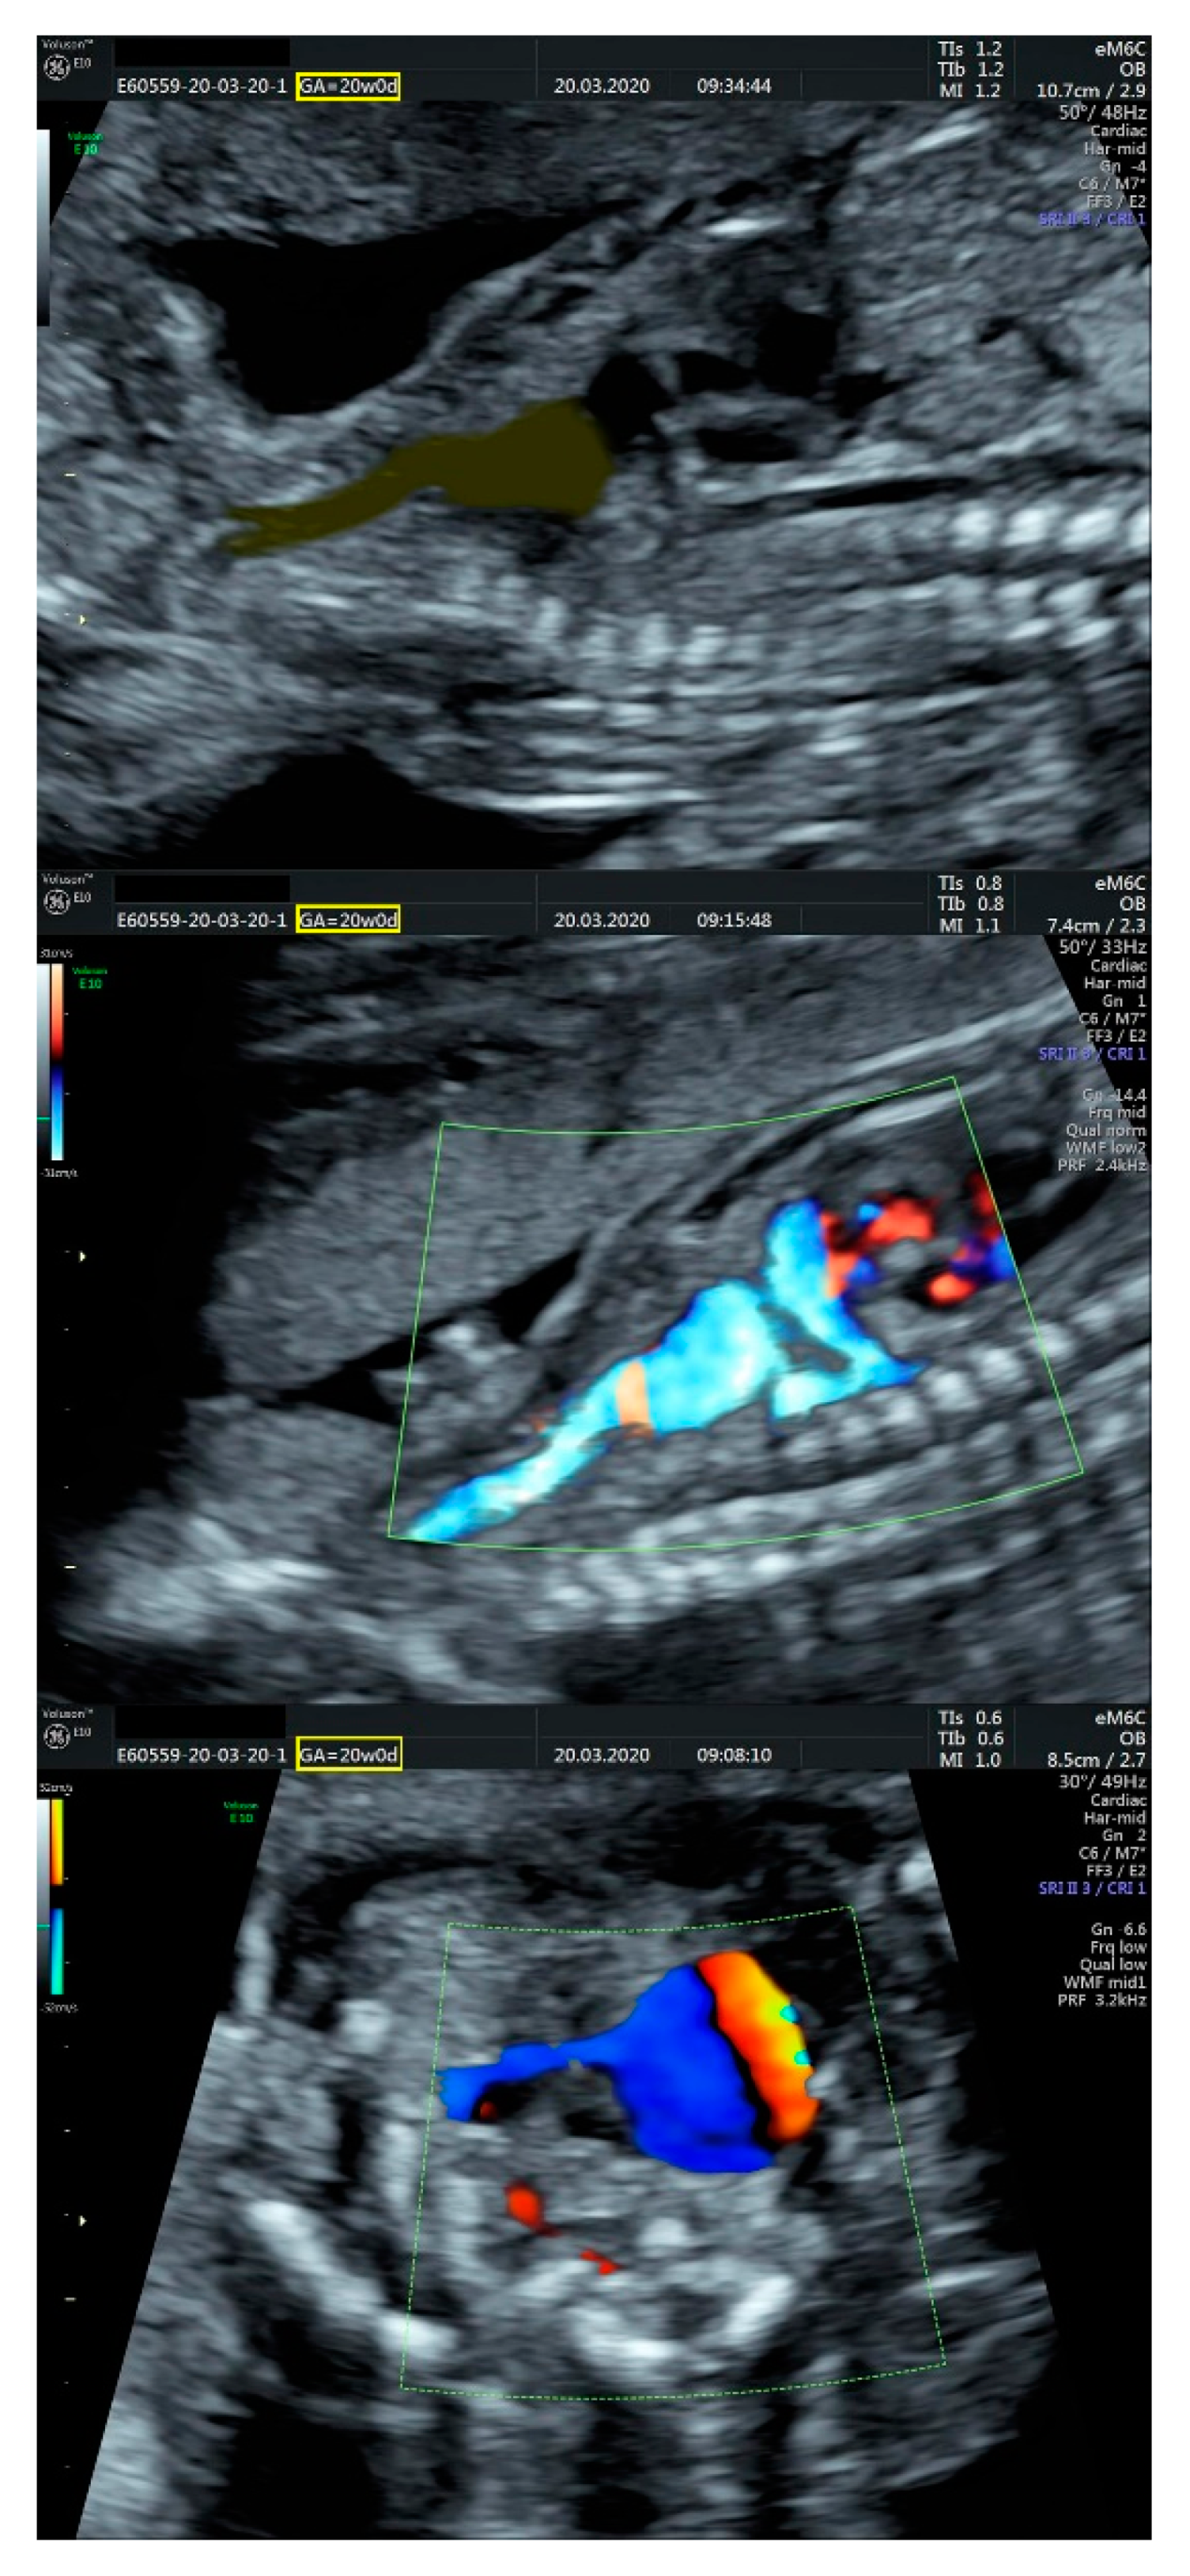

- ventricular septal defect, coarctation of the aorta, and a vascular formation located superior from the aortic arch with the appearance of an arteriovenous fistula;

- aneurysmal dilation located above the pulmonary trunk bifurcation and a dilated left common carotid artery with a retrograde flow;

- minor ventricular septal defect with a normal ductus venosus triphasic flow.